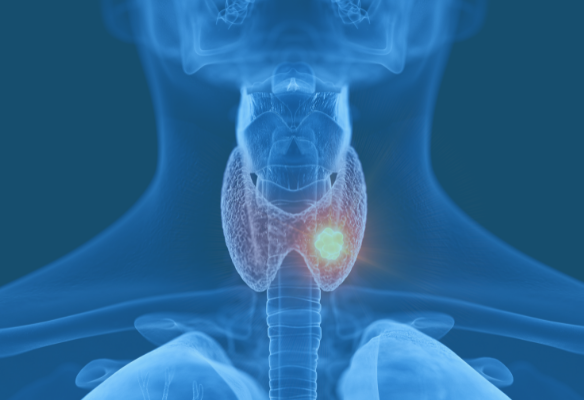

NFCR-funded researchers are all, in some way, using cancer genomics, but there are still certain cancer types that are most impacted by their projects. Specifics about those projects – as well as the cancer diagnoses – are outlined on the “Cancer Types” pages below.